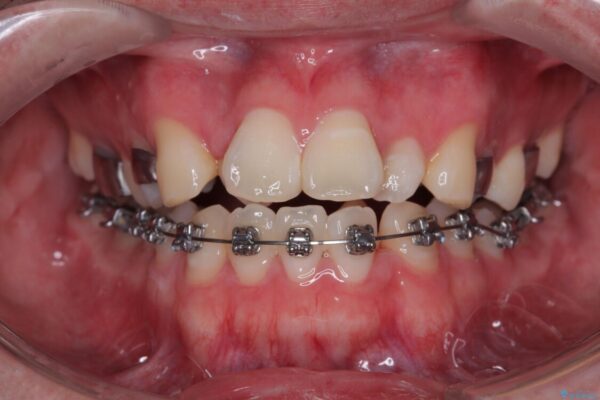

治療途中

• 1年でここまで変わる!歯列のがたつきと正中のズレを改善した矯正治療(メタルブラケット×MARPE) 治療途中画像